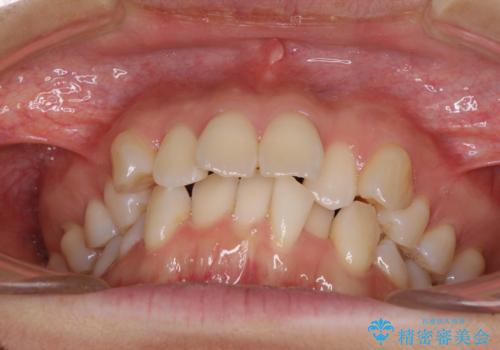

- 前歯のデコボコと口元の突出感を気にして来院された患者様です。

非抜歯矯正ではデコボコを解消することでより口元が突出してしまうため、上下左右の小臼歯4本の抜歯を行い、ワイヤー装置による矯正治療を行うこととしました。

もう少し口元の突出感を改善したかったのですが、舌の突出癖が影響し下顎前歯が唇側に押させる仕上がりとなりました。